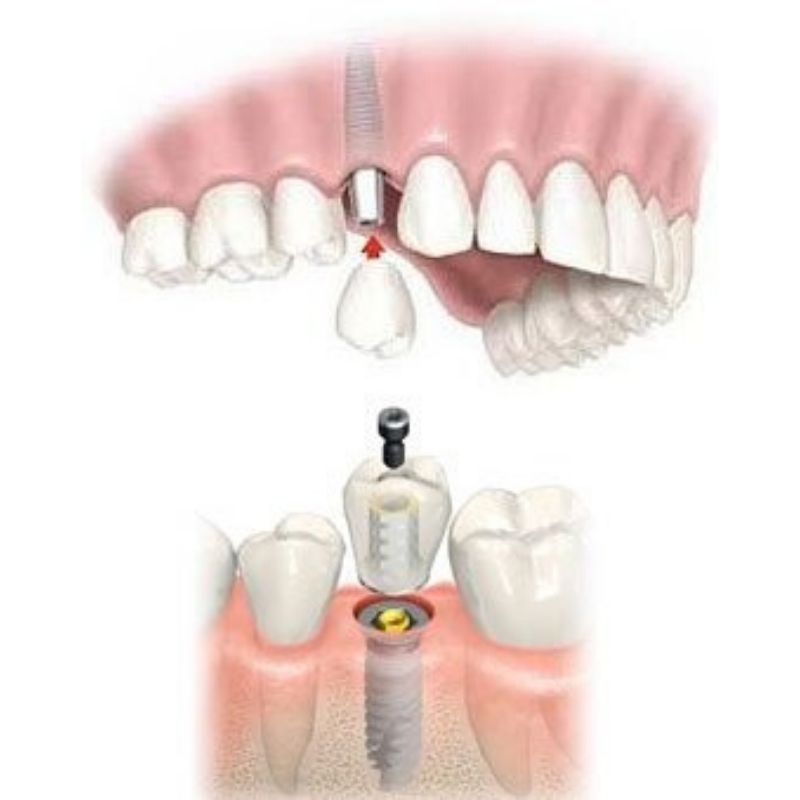

Single Tooth Options

When a tooth is lost, an implant is essentially a fake tooth root. After the implant is placed and allowed to heal in, a tooth is attached. With 3-D x-ray and digital planning, the results can be excellent.